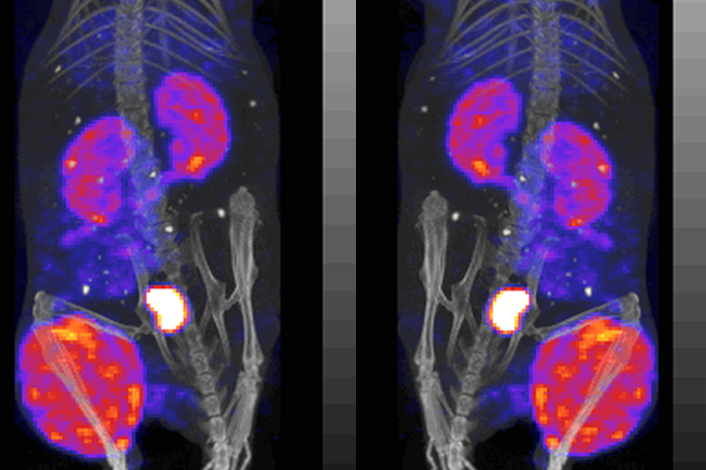

This image is an example of the pharmacokinetic data obtainable from a single animal, in this case imaged on the NanoSPECT/CT camera with image quantiation of three acquisitions. Typical projections of one tomographic acquisition obtained on the NanoSPECT/CT camera of a tumored mouse receiving a radiolabeled agent and imaged at 3 hr post injection.